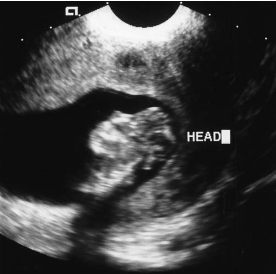

The sonographic finding in this image is most suspicious for:

ventriculomegaly